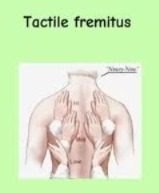

Tactile fremitus (ટેક્ટાઇલ ફ્રેમિટસ):

- ટેક્ટાઇલ ફ્રેમિટસ એ પાલપેશનની એક ટેકનિક છે જેનો ઉપયોગ સ્પીચને કારણે ચેસ્ટમાં ટ્રાન્સમિટ થતાં વાઇબ્રેશન ને અસેસ કરવામાં આવે છે. જેમાં હેલ્થ કેર પર્સનલ પોતાના હેન્ડને ઈમેજમાં દર્શાવ્યા મુજબ તે એરિયામાં પ્લેસ કરે છે અને પેશન્ટને બોલવા માટે કહે છે અને ચેસ્ટના ભાગે વાઇબ્રેશન ફિલ કરે છે.

- જો ફ્રેમિટસમાં વધારો જોવા મળે તો તે ન્યુમોનિયા જેવી કન્ડિશન ઇન્ડિકેટ કરે છે પરંતુ ફ્રેમિટસમાં ઘટાડો જોવા મળે તો તે પ્લુરલ ઇફયુઝન જેવી કન્ડિશન ઇન્ડિકેટ કરે છે.